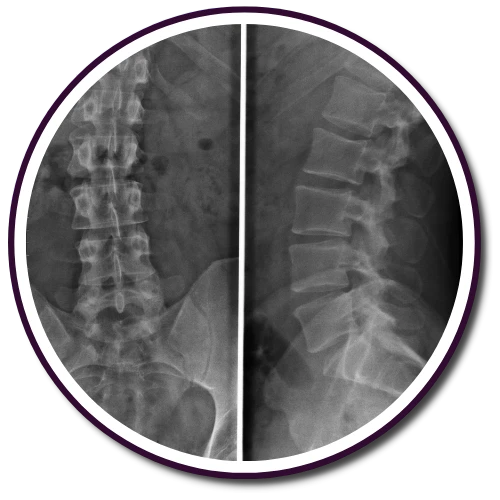

We offer a wide range of chiropractic therapies and pain management methods to address conditions such as low back pain or severe back issues. Our clinic in Daytona Beach focuses on determining the root cause of your discomfort and using natural healing techniques to achieve your wellness goals. Our team is dedicated to answering all your questions and assisting you in harnessing your nerve system's natural ability to heal.